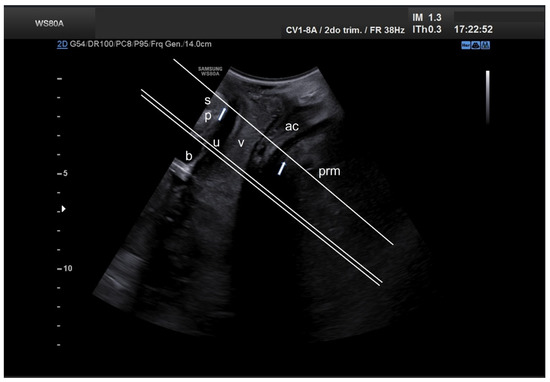

2. Materials and Methods